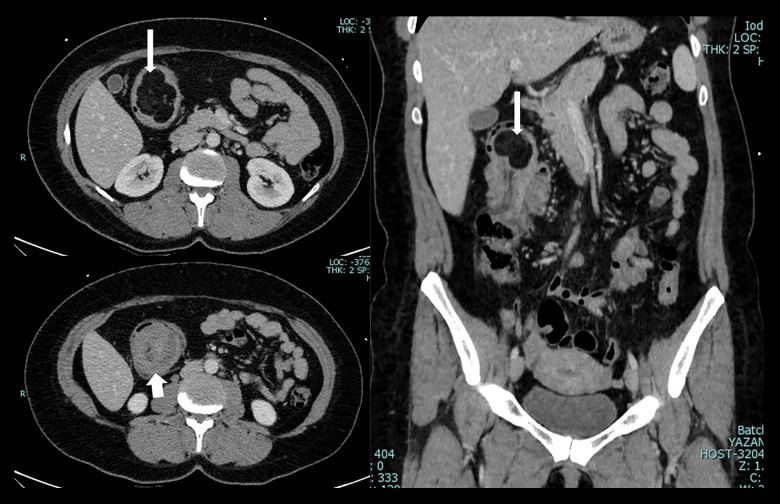

成人肠套叠(AI)是一种罕见的疾病,具有多种临床表现和管理挑战。尽管罕见,但了解其流行病学,临床特征和区分良恶性导点的预测因素对有效治疗至关重要。本研究旨在评估病理性人工智能患者的人口学和临床特征,并探讨与恶性导点相关的因素。材料与方法回顾性分析2014年1月1日至2024年1月1日诊断为AI的bb0 ~ 18岁患者的病历。根据肠套叠的部位和病因对患者进行分类。评估恶性导点的预测因素,包括年龄、性别、表现症状、位置和肠套叠大小。复习计算机断层扫描(CT)图像以确认诊断。排除短暂性小肠肠套叠及饲管相关肠套叠。结果10年内共发现病理性人工智能26例,男性占69.2%,平均年龄53.3岁。腹痛是最常见的症状(65.4%),诊断为肠梗阻的病例占23.1%。CT扫描是主要诊断方式(92.3%)。结肠肠套叠最为常见(53.8%),手术治疗较为常见(69.2%)。组织病理学检查显示大多数病例(57.7%)为良性铅点,以脂肪瘤和息肉最为常见。直肠出血与恶性导点显著相关(P=0.011)。结论人工智能具有多种临床特征。它主要影响结肠。直肠出血提示恶性铅点的可能性较大。多学科方法对于最佳的基于病例的管理至关重要。

BACKGROUND Adult intussusception (AI) is a rare condition with diverse clinical presentations and management challenges. Despite its rarity, understanding its epidemiology, clinical features, and predictive factors distinguishing benign and malignant lead points is crucial for effective management. This study aimed to assess the demographic and clinical characteristics of patients with pathological AI and examine factors associated with malignant lead points. MATERIAL AND METHODS Medical records of patients aged >18 years with diagnosis of AI between January 1, 2014, and January 1, 2024 were retrospectively analyzed. Patients were classified based on location and etiology of intussusception. Predictive factors for malignant lead points were assessed, including age, sex, presenting symptoms, location, and size of intussusception. Computed tomography (CT) scan images were reviewed for diagnosis confirmation. Transient small bowel intussusceptions and intussusceptions related to feeding tubes were excluded. RESULTS Twenty-six cases of pathological AI were identified over 10 years, with a male predominance (69.2%) and a mean age of 53.3 years. Abdominal pain was the most common presenting symptom (65.4%), with bowel obstruction diagnosed in 23.1% of cases. CT scans were the primary diagnostic modality (92.3%). Colocolic intussusceptions were most prevalent (53.8%), and surgical management was common (69.2%). Histopathological examination revealed benign lead points in the majority (57.7%) of cases, with lipomas and polyps being the most common. Bleeding per rectum was significantly associated with malignant lead points (P=0.011). CONCLUSIONS AI presents with diverse clinical features. It predominantly affects the colon. Bleeding per rectum indicates a higher likelihood of malignant lead points. A multidisciplinary approach is essential for optimal case-based management.